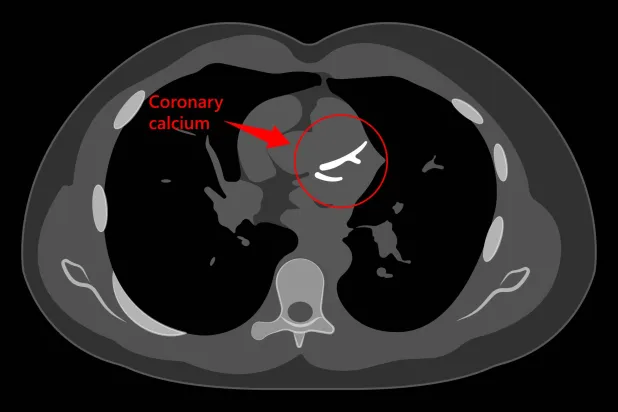

ضرورة الفحص بالأشعة المقطعية للتحقق من مرض الشريان التاجي.